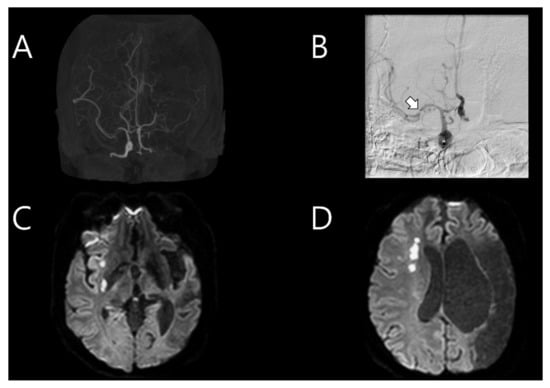

A 33-year-old woman was previously admitted with global aphasia at gestational week 7. She received daily injections of 2 cc of progesterone and low-molecular-weight heparin due to her history of two previous pregnancy losses at 25 and 28 weeks of gestation, respectively. These miscarriages each happened 2 and 3 years before the stroke, spontaneously after cervical ripening. Neurological examination revealed alert mental status, global aphasia, and right hemiparesis (Medical Research Council (MRC) grade, 3/3), indicating a National Institute of Health Stroke Scale (NIHSS) score of 11. Brain magnetic resonance imaging (MRI) revealed a stroke in the left middle cerebral artery (MCA) territory (Figure 1A). Intravenous tissue plasminogen activator (tPA) was administered, with an onset-to-door time of 1 h and 23 min. Intra-arterial thrombectomy was also subsequently performed. Transfemoral cerebral angiography (TFCA) revealed the total occlusion of the distal portion of the left internal carotid artery (ICA) with a massive thrombus. It was clearly a by-product of arterial dissection nearby; significantly, the operator felt the existence of the flap even before any further invasive procedure was practiced. However, the procedure could not be continued because of the severe headache experienced by the patient (Figure 1B). A brain MRI performed the following day revealed acute infarction in the left MCA territory with multifocal embolic infarction in the bilateral hemispheres and the complete occlusion of the left ICA (Figure 1C,D). Transthoracic echocardiography (TTE) used to verify the cardioembolic source revealed mild akinesia; however, the heart appeared normal on cardiac computed tomography (CT). The cardiac CT findings suggested acute pulmonary thromboembolism in the left lower lobe. Considering the massive thrombus in the left MCA and suspected pulmonary thromboembolism, warfarin was administered. Autoimmune disease screening tests, including those for anticardiolipin antibody and anti-beta-2 glycoprotein I antibody, were conducted twice, with negative results both times. Additionally, coagulopathy screening tests, including those for antithrombin antibody 87.7% (normal range 75–125), protein C antigen 111.8% (normal range 72–160), and protein S antigen 108.4% (normal range 60–150), were negative. The patient was discharged after her neurological symptoms improved (NIHSS score of 3).

Figure 1. (A) Initial brain magnetic resonance imaging (MRI) after the first event showing stroke in the left middle cerebral artery (MCA) territory. (B) Immediate transfemoral cerebral angiography showing total occlusion of the distal portion of the left internal carotid artery (ICA). (C) Follow-up brain MRI on the following day showing acute infarction in the left MCA territory with multifocal embolic infarction in the bilateral hemispheres. (D) Magnetic resonance angiography showing complete occlusion of the left ICA.